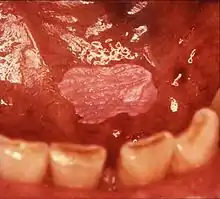

| Leukoplakia on the inside of the cheek | |